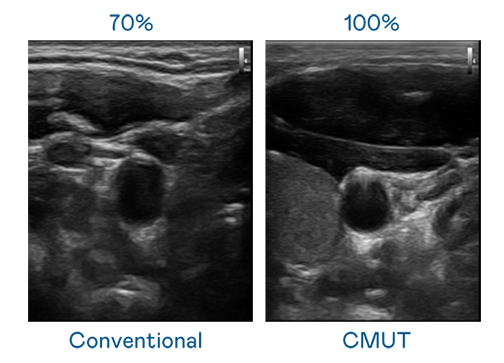

CMUT 技术是一种用电容式微机电元件来产生超音波讯号的技术。与传统 PZT 压电式技术相比,CMUT 频宽增加 30%,更宽频的超音波讯号让影像解析度大幅提升,是实现高影像品质医疗超音波扫描、促进精准医疗发展的关键技术。

大频宽带来超清晰影像

超音波影像的解析度高低,首先取决于探头能发出的讯号频宽。彩神Vll CMUT 可提供高清晰的超音波讯号,提供高频宽、高灵敏度、影像纹理细节更高的超音波影像,协助医护人员缩短影像判读时间及利用精准的医疗影像进行诊断。